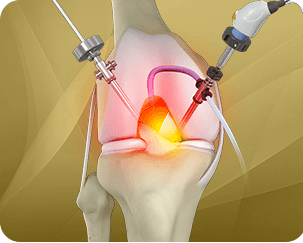

Robotic-assisted knee replacement surgery is an alternative to the conventional knee replacement procedure. It is performed using robotic-arm technology that allows your surgeon to precisely perform the surgery through a smaller incision as compared to traditional surgery. Dr. Liddell performs both total knee and partial knee replacement in a minimally invasive manner with precision under robotic assistance.